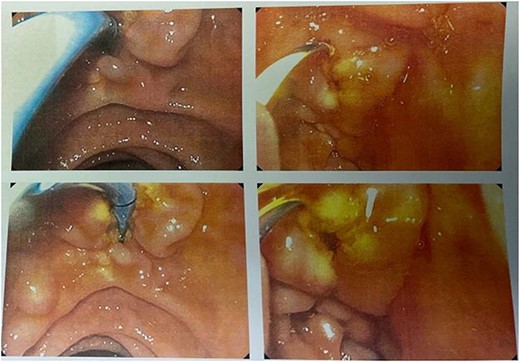

The subsequent EUS confirmed the presence of an IPMN-like lesion, although it was not possible to detect a connection with the pancreatic duct, because of the size of the cyst. There was no evidence of worrisome features or solid lesions (Fig. 2).